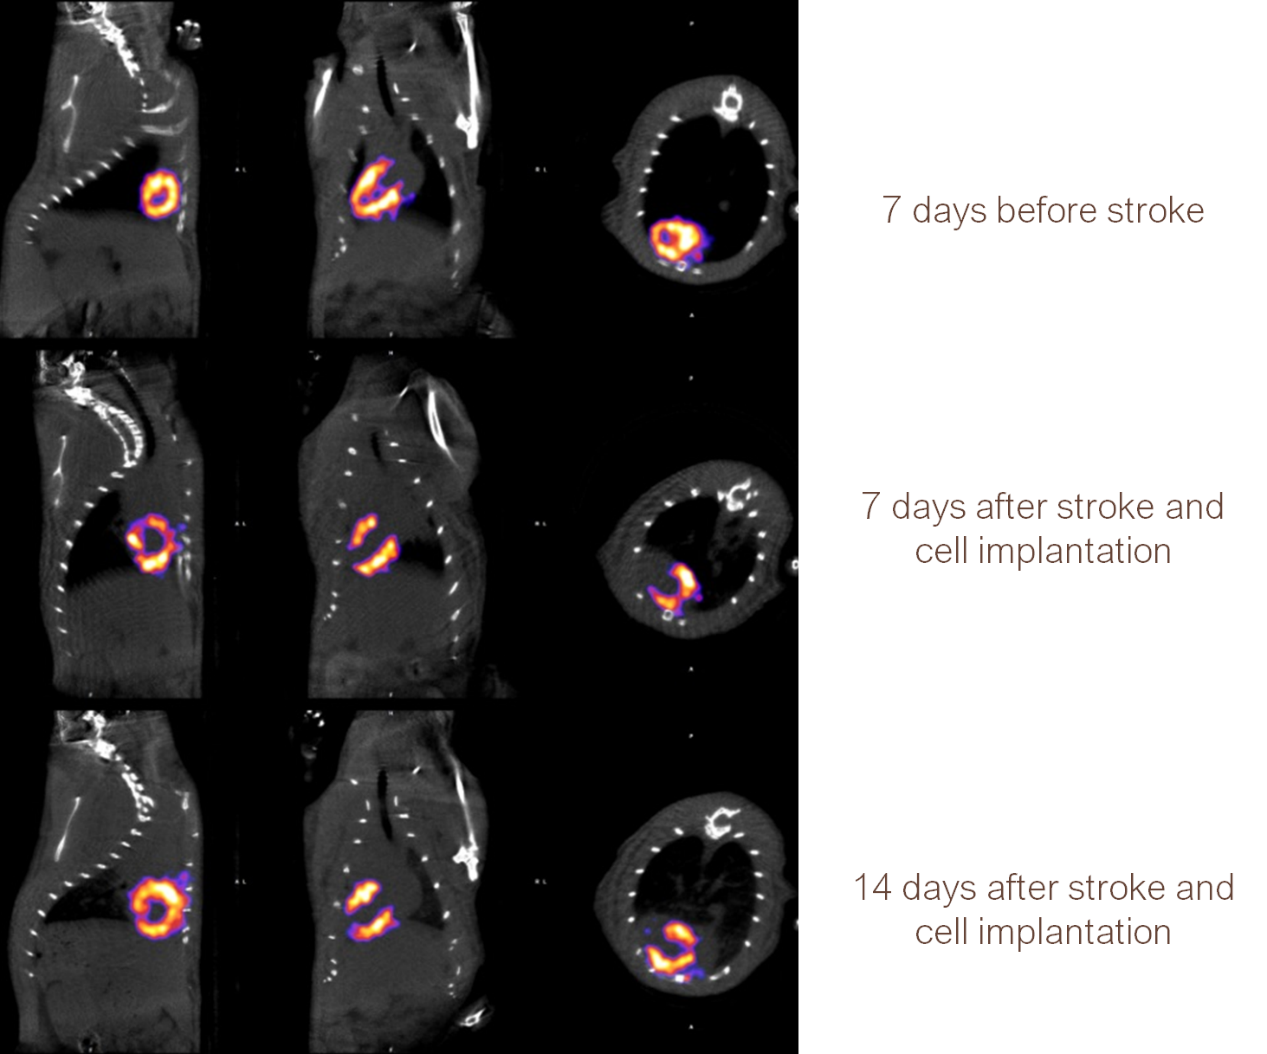

2、心血管SPECT成像

小鼠心肌SPECT成像:藥物99mTc-MIBI反映注藥當(dāng)時(shí)情況下的心肌血流灌注量,63.27 MBq (1.71 mCi) @ start acquisition,采集時(shí)間40min。

小鼠心肌成像.png

大鼠心血管中風(fēng)模型,中風(fēng)前后及用藥后,觀察心臟血流狀態(tài)。

大鼠心血管成像.png